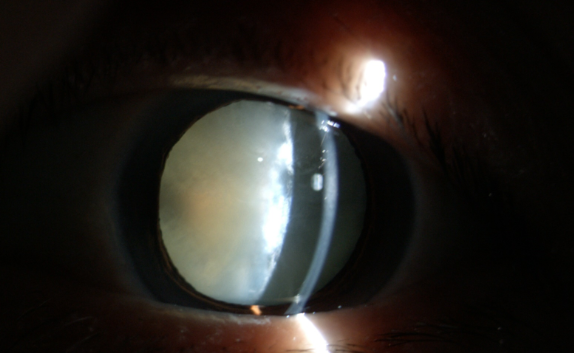

糖尿病為什么更易得白內(nèi)障

【文章導(dǎo)讀】在臨床中,很多糖尿病患者不太重視診治,尤其忽視糖尿病導(dǎo)致的多種眼科并發(fā)癥,如白內(nèi)障。糖尿病友得白內(nèi)障較普通人來說有三個特點:

在臨床中,很多糖尿病患者不太重視診治,尤其忽視糖尿病導(dǎo)致的多種眼科并發(fā)癥,如白內(nèi)障。糖尿病友得白內(nèi)障較普通人來說有三個特點:

(1)糖尿病患者比一般老年人白內(nèi)障發(fā)生率高;

(2)糖尿病患者比一般老年人白內(nèi)障發(fā)生早;

(3)糖尿病患者比一般老年人白內(nèi)障成熟快。

糖尿病合并白內(nèi)障應(yīng)盡早手術(shù)

糖尿病患者與一般的白內(nèi)障患者不同,因為糖友們常會伴有糖尿病性視網(wǎng)膜病變和眼部其他損害。醫(yī)生要求每3~6個月進(jìn)行一次眼科檢查,目的是延緩甚至阻斷糖尿病眼病的發(fā)生和發(fā)展。

白內(nèi)障癥狀

糖尿病患者合并白內(nèi)障盡早手術(shù)的原因:白內(nèi)障發(fā)生后,不但使患者視力產(chǎn)生障礙甚至失明,還直接影響到醫(yī)生對眼底的檢查和治療,因為渾濁的晶狀體阻斷了進(jìn)出光線。因此,糖友們的白內(nèi)障手術(shù)治療,既能解除視力障礙,還能掃除糖尿病視網(wǎng)膜病變的檢查、治療障礙,所以應(yīng)盡早手術(shù)。